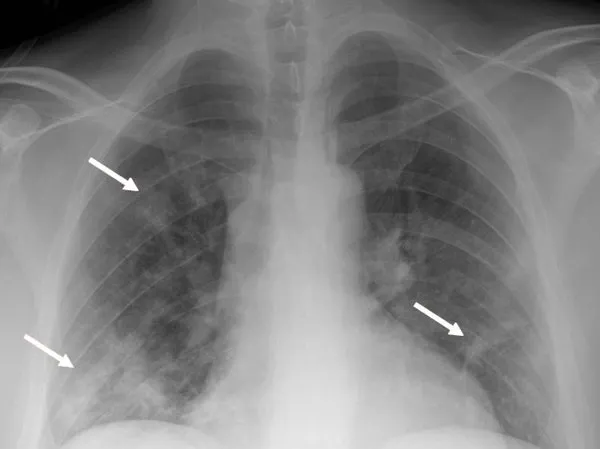

BU DURUMLARDAN HERHANGİ BİRİ VARSA KİŞİ HASTALIĞI AĞIR GEÇİRİYOR

Bu amaçla öncelikle interferon sinyal yolladığında görev alan genler ve ayrıca kan gruplarını belirleyen gen bölgelerinde olmak üzere toplam 20'den fazla gen bölgesindeki genetik varyasyonlar inceleniyor. Eğer bu varyasyonlardan herhangi birisi mevcutsa bu durum kişinin Kovid- 19'u ağır geçirebileceğini gösteriyor" dedi.